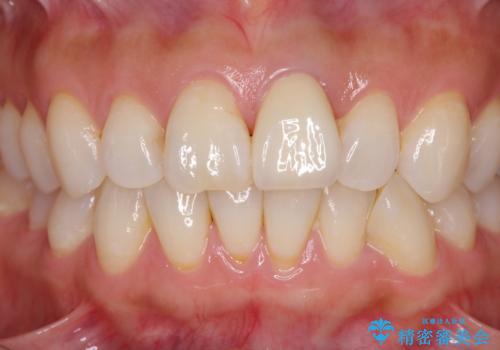

変色とともに、捻れていたことも気になっていたので、その両方を解決させることとしました。

オーダーメイドタイプのクラウンを選択いただいたので、まるで天然の歯と見間違うほど自然に仕上がり、患者様には大変満足していただきました。